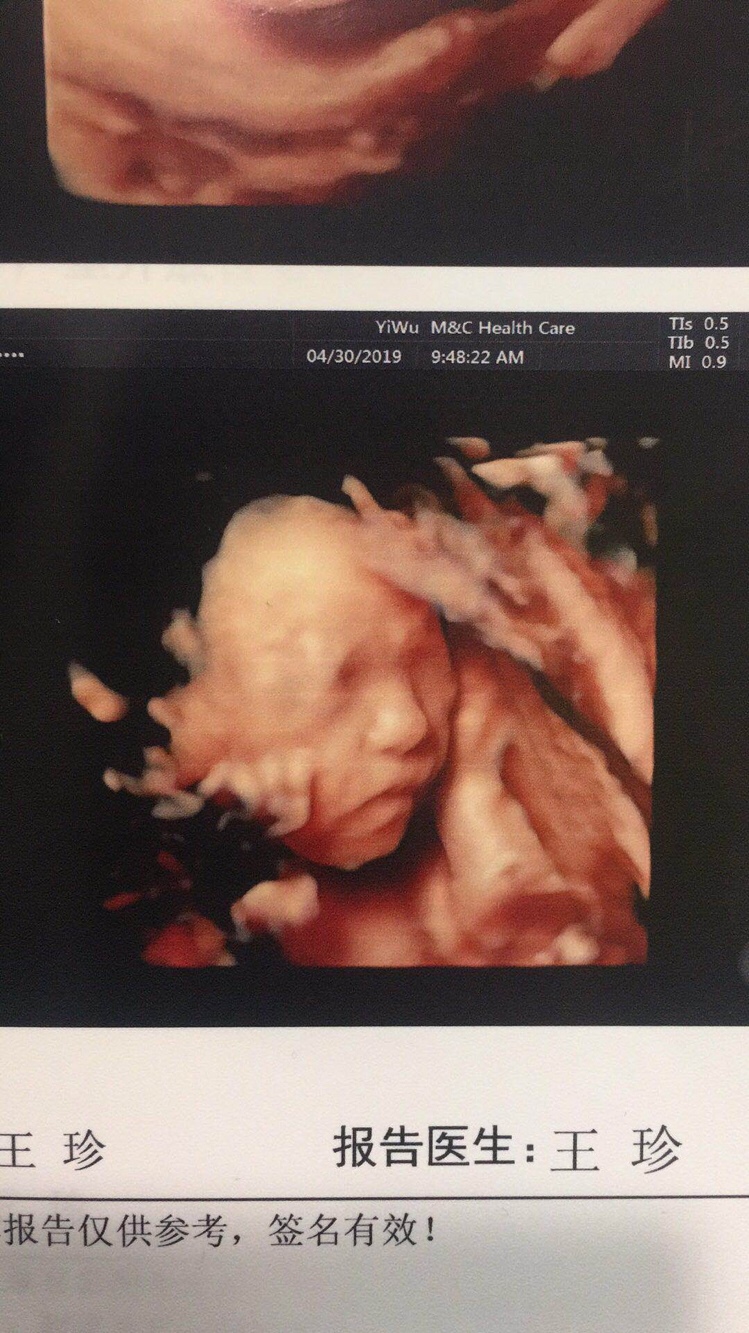

宝宝4个月29天

应该是男宝宝吧